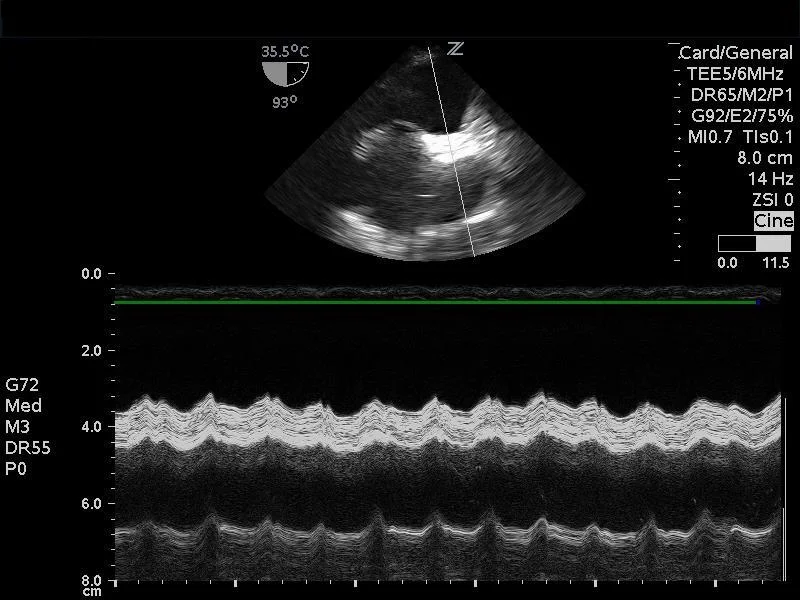

We have multiple tools in the ED that allow us to assess patients rapidly. But of course, you must use the right tool for the patient. Transthoracic echo (TTE) can be useful to assess a patient in shock and is our go-to tool when we approach a patient with hemodynamic decompensation or shock. But what happens when TTE fails you?